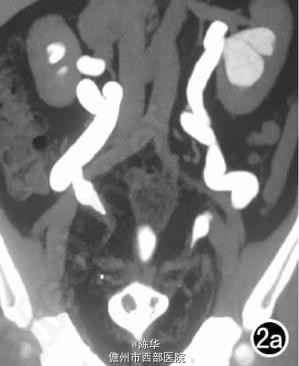

腹部B超示双肾增大,双肾慢性肾病声像;双肾中度积液伴双输尿管上段扩张。 IVPshi双侧输尿管中或下段梗阻。 膀胱造影:经尿道置管后,注射对比剂充盈膀胱,膀胱下半部先充盈,继续灌注对比剂后见膀胱完全显影,膀胱形态异常,呈“倒葫芦状”(图1)。 CT增强扫描行延迟期 MPR重组,见双侧肾盂、肾盏扩张积液;双侧输尿管纡曲、扩张,下端呈鸟嘴样变窄;膀胱变形、体积减小(图2); MRI平扫示双侧肾盂、肾盏扩张积液,双侧输尿管扩张并下端鸟嘴样变窄,盆腔内多量脂肪沉积,分布于膀胱、直肠周围,T1WI、T2WI呈明显高信号,T2WI抑脂像呈稍高信号,膀胱受压变形、体积减小(图3a~c); MRU示双侧肾盂肾盏扩张、积液,双侧输尿管显著纡曲、扩张,下端鸟嘴样变窄,管壁光整,膀胱变形、体积较小、位置抬高(图3d)。